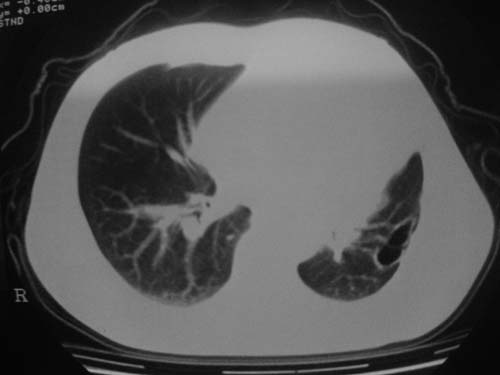

男性39岁,干咳一个月,最近胸憋气短,自己感觉发烧出汗,要求拍ct

图像质量较差请多包含,考虑肺癌,肺结核不除外,大家是否同意这种看法,请各位老师指教

左肺上叶中央型肺癌并阻塞性肺不张。

考虑:左肺上叶中央型肺癌并阻塞性肺不张。左肺下叶囊肿或支扩。

左侧肺癌伴阻塞性肺炎,纵隔转移。

1.左侧肺癌伴阻塞性肺炎,纵隔转移。2.左下肺大泡。3.左下肺感染

纵隔淋吧结肿大

心包积液

双侧胸膜增厚

左肺上叶中央型肺癌并阻塞性肺不张,纵隔淋巴结转移。